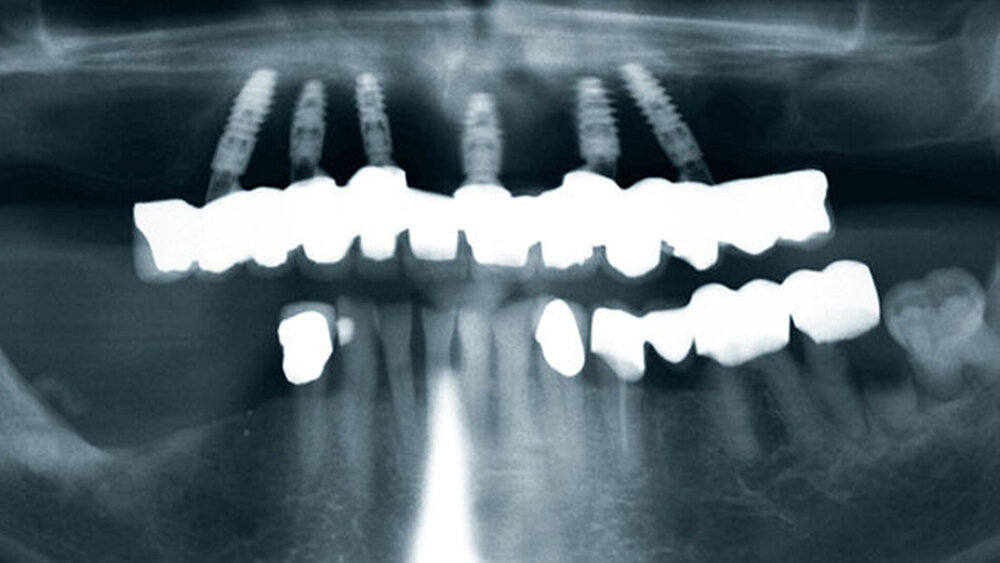

Buhtz: Korrekt, die Voraussetzung ist lediglich die Generierung von DICOM- und STL-Daten, die im Computer exakt übereinandergelegt werden können. Dann erfolgen die Behandlungsplanung wie gewohnt mit ICX-Magellan und die provisorische ‧Versorgung mit dem präfabizierten, chairside hergestellten verklebten PMMA-Provisorium (ICX-‧Smile‧bridge). Seit eineinhalb Jahren arbeiten wir zudem mit dem medentis Fräszentrum Denta5 zusammen.

Buhtz: Wir schicken die Scan-Daten, ein Wax-up und ggf. das Modell mit den Laborimplantaten an das medentis-Fräszentrum und erhalten zwei Tage später die verschraubte Unterkonstruktion. Denta 5 gibt es bereits seit einigen Jahren. Doch erst seit wir einen eigenen Modellscanner haben, stellen wir verschraubte Brücken auf diese Weise her. Jetzt habe ich eine Zahntechnikerin, die damit gut klarkommt. Full-arch-Versorgungen sind bei uns allerdings nicht das Tagesgeschäft, wir machen das vielleicht zehn- bis zwanzigmal pro Jahr. Unsere Patientenklientel ist in der Regel nicht zahnlos.

Buhtz: Egal, wie viele Implantate ich wo setze – am Anfang stehen in meiner Praxis meist eine DVT-Aufnahme und eine 3D-Planung. Ohne Schablone setze ich heute nur noch in absoluten Ausnahmefällen ein Implantat. Die Sicherheit und die gute Planbarkeit reduzieren die Angst der Patienten vor dem Eingriff und erleichtern die Aufklärung. Artefaktarme DVT-Aufnahmen sind natürlich für die Präzision entscheidend.

Die ideal prothetisch ausgerichtete Implantatposition ist der wohl wichtigste Erfolgsfaktor in der Implantologie. Mit ICX-Magellan lässt sich das einfach, schnell und kostengünstig realisieren.